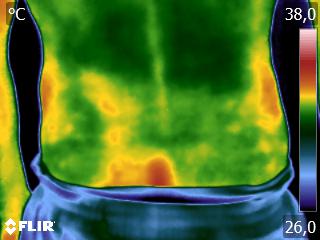

Quando se tem a formação da Técnica Termofuncional, vocês aprenderão usar a técnica Termoguiada para aplicar seus métodos/técnicas de forma mais assertiva, promovendo melhores resultados.

A técnica Termoguiada deve ser usada toda vez que você precisa, na clínica, de precisão imediata, principalmente quando os métodos/técnicas precisarem ser exatamente aplicados num tecido específico.